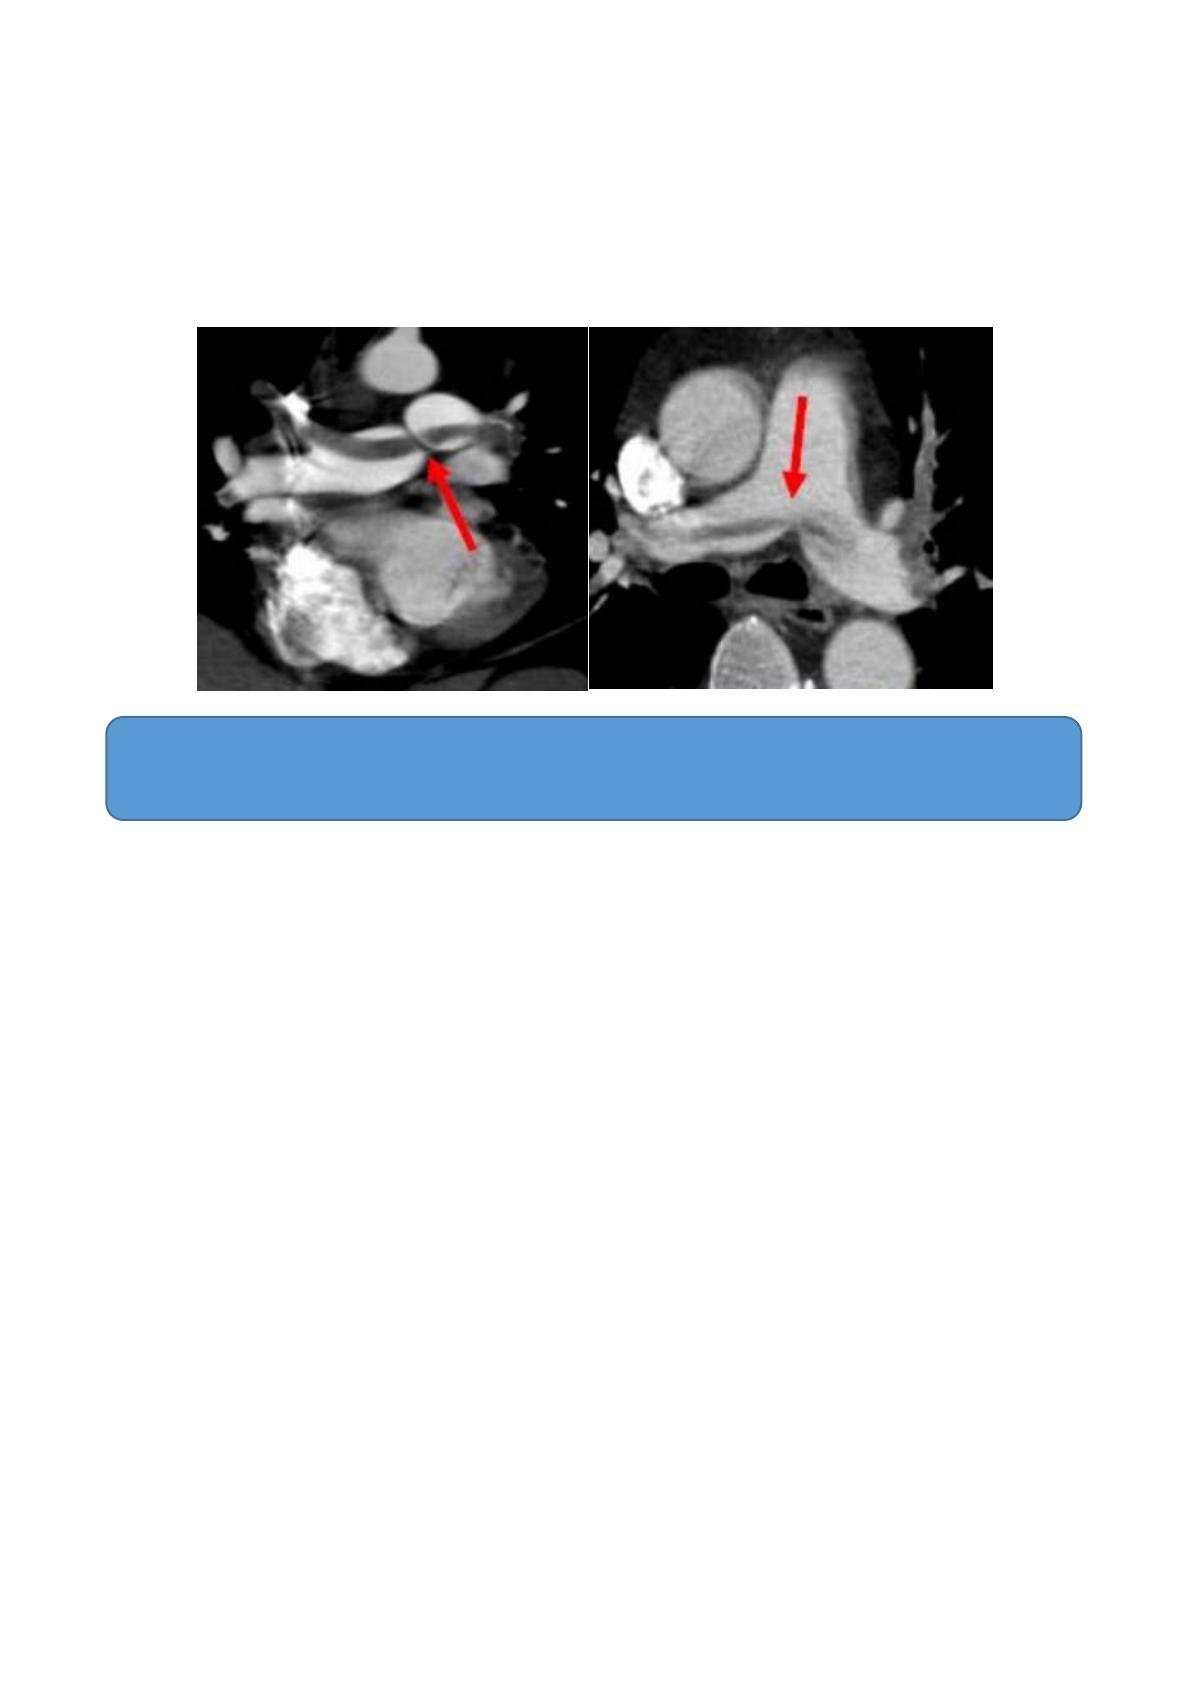

cardiorespiratoire (8 cas). Les critères scannographiques majeurs étaient : un index

d’obstruction > 60 % (18 cas), un rapport VD/VG > 0,9 (20 cas), un bombement septal (15

cas), une dilatation de l’artère pulmonaire > 30 mm (21 cas), une dilatation de la VCS ou de la

veine azygos (15 cas) et un reflux veineux systémique (7 cas).